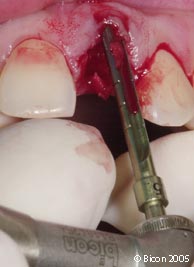

39. | 作减张切口以便于一体化基台冠的就位。 |

40. | 初步就位的一体化基台冠。 |